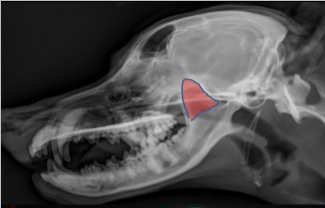

Tympanic Bulla

ID.

Horizontal Ear Canal